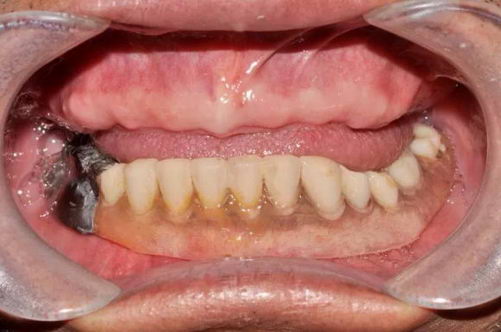

【张叔叔口内缺牙情况】

【种牙前】